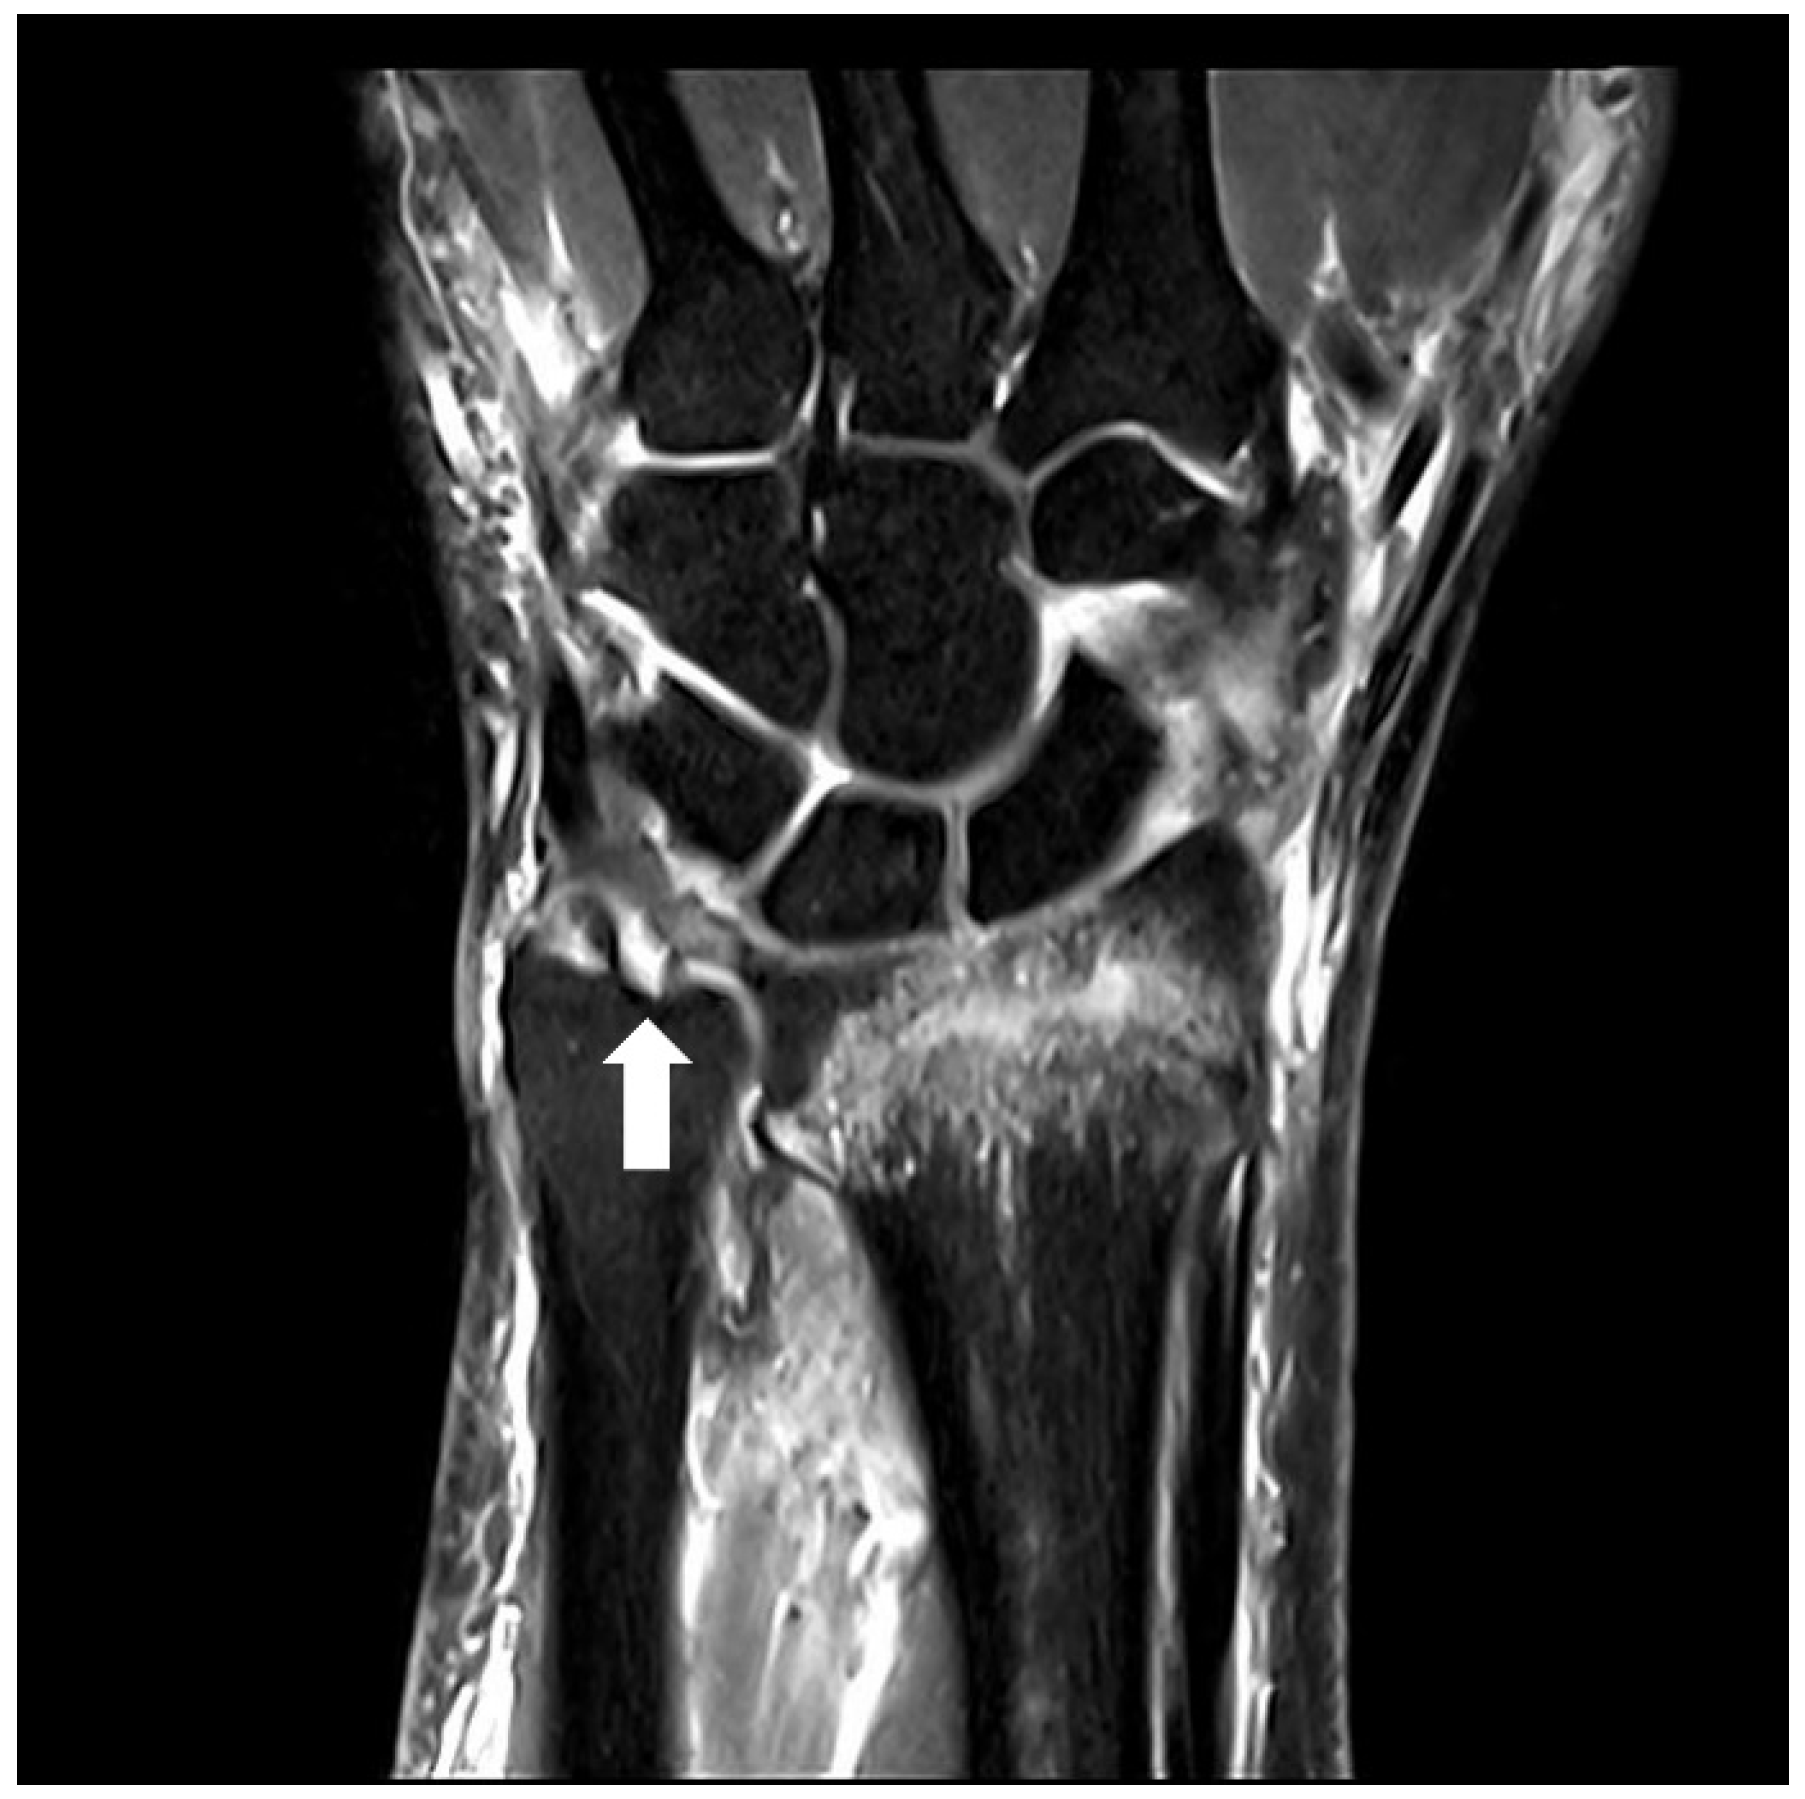

The severity of deformity in distal radius fracture was assessed by measuring the length of ulnar variance, angle of radial inclination, and angle of dorsal angulation at the initial visit and before manual reduction, based on wrist anteroposterior and lateral view of plain radiographs as previously described [16]. Ulnar variance was assessed by the distance between perpendicular lines to the radial axis through the dorsal radial cortex at the radioulnar joint and the distal articular surface of the ulna on the anteroposterior radiograph, while radial inclination was determined by the angle between the perpendicular line to the radial axis and the line joining the distal tip of the radial styloid and the central reference point of distal sigmoid notch on the anteroposterior radiograph [17,18]. The angle of dorsal angulation was measured by the angle created between the perpendicular line to the radial axis and the line joining the most distal points of the dorsal and ventral rims of the distal articular surface of the radius on the lateral radiograph. AO/OTA classification was used in defining the classification and severity of a distal radius fracture [19]. Type A was considered an extra-articular fracture, and Type C was considered an intra-articular fracture. Ulnar styloid fractures were classified based on the fracture line locations. The ulnar styloid status was categorized as intact ulnar styloid, ulnar styloid base fractures, or ulnar styloid tip fractures. Parameters on the plain radiographs were measured using a digital caliper in the Picture Archiving and Communication System by two orthopedic surgeons who were blind to this study, and their measurements were averaged. BMD was measured within one month before the operation in all patients at the lumbar spine and hip using a DEXA scanner (Hologic, Bedford, MA, USA). DEXA for the lumbar spine and the proximal femur was performed by using standard techniques according to the manufacturer and the International Society for Clinical Densitometry guidelines [20]. Preoperative wrist MRI was interpreted by a blinded musculoskeletal radiologist who was not involved in this study. A TFCC foveal tear was defined as a loss of continuity of the foveal fiber or complete bony avulsion with the foveal insertion attached to the fracture fragment (Figure 1) [21].

Figure 1.

Preoperative magnetic resonance images of the left wrist. Proton density-weighted turbo spin-echo imaging in the coronal plane. The proximal component of the triangular fibrocartilage complex (TFCC) is torn at the foveal attachment (white arrow), compatible with a TFCC foveal tear.